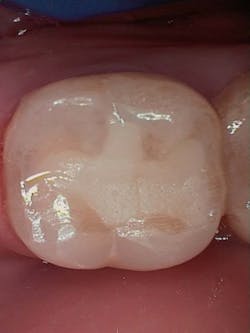

Figure 1 shows a large radiolucency on the mesial and a small radiolucency on the occlusal of tooth 31. Figure 2 shows an initial caries lesion on the distal pit and a leaking occlusal composite. Tooth 31 was sensitive to cold but normal to chewing, bite, and heat. Selective caries removal was used to prevent pulp exposure and preserve the marginal ridge.